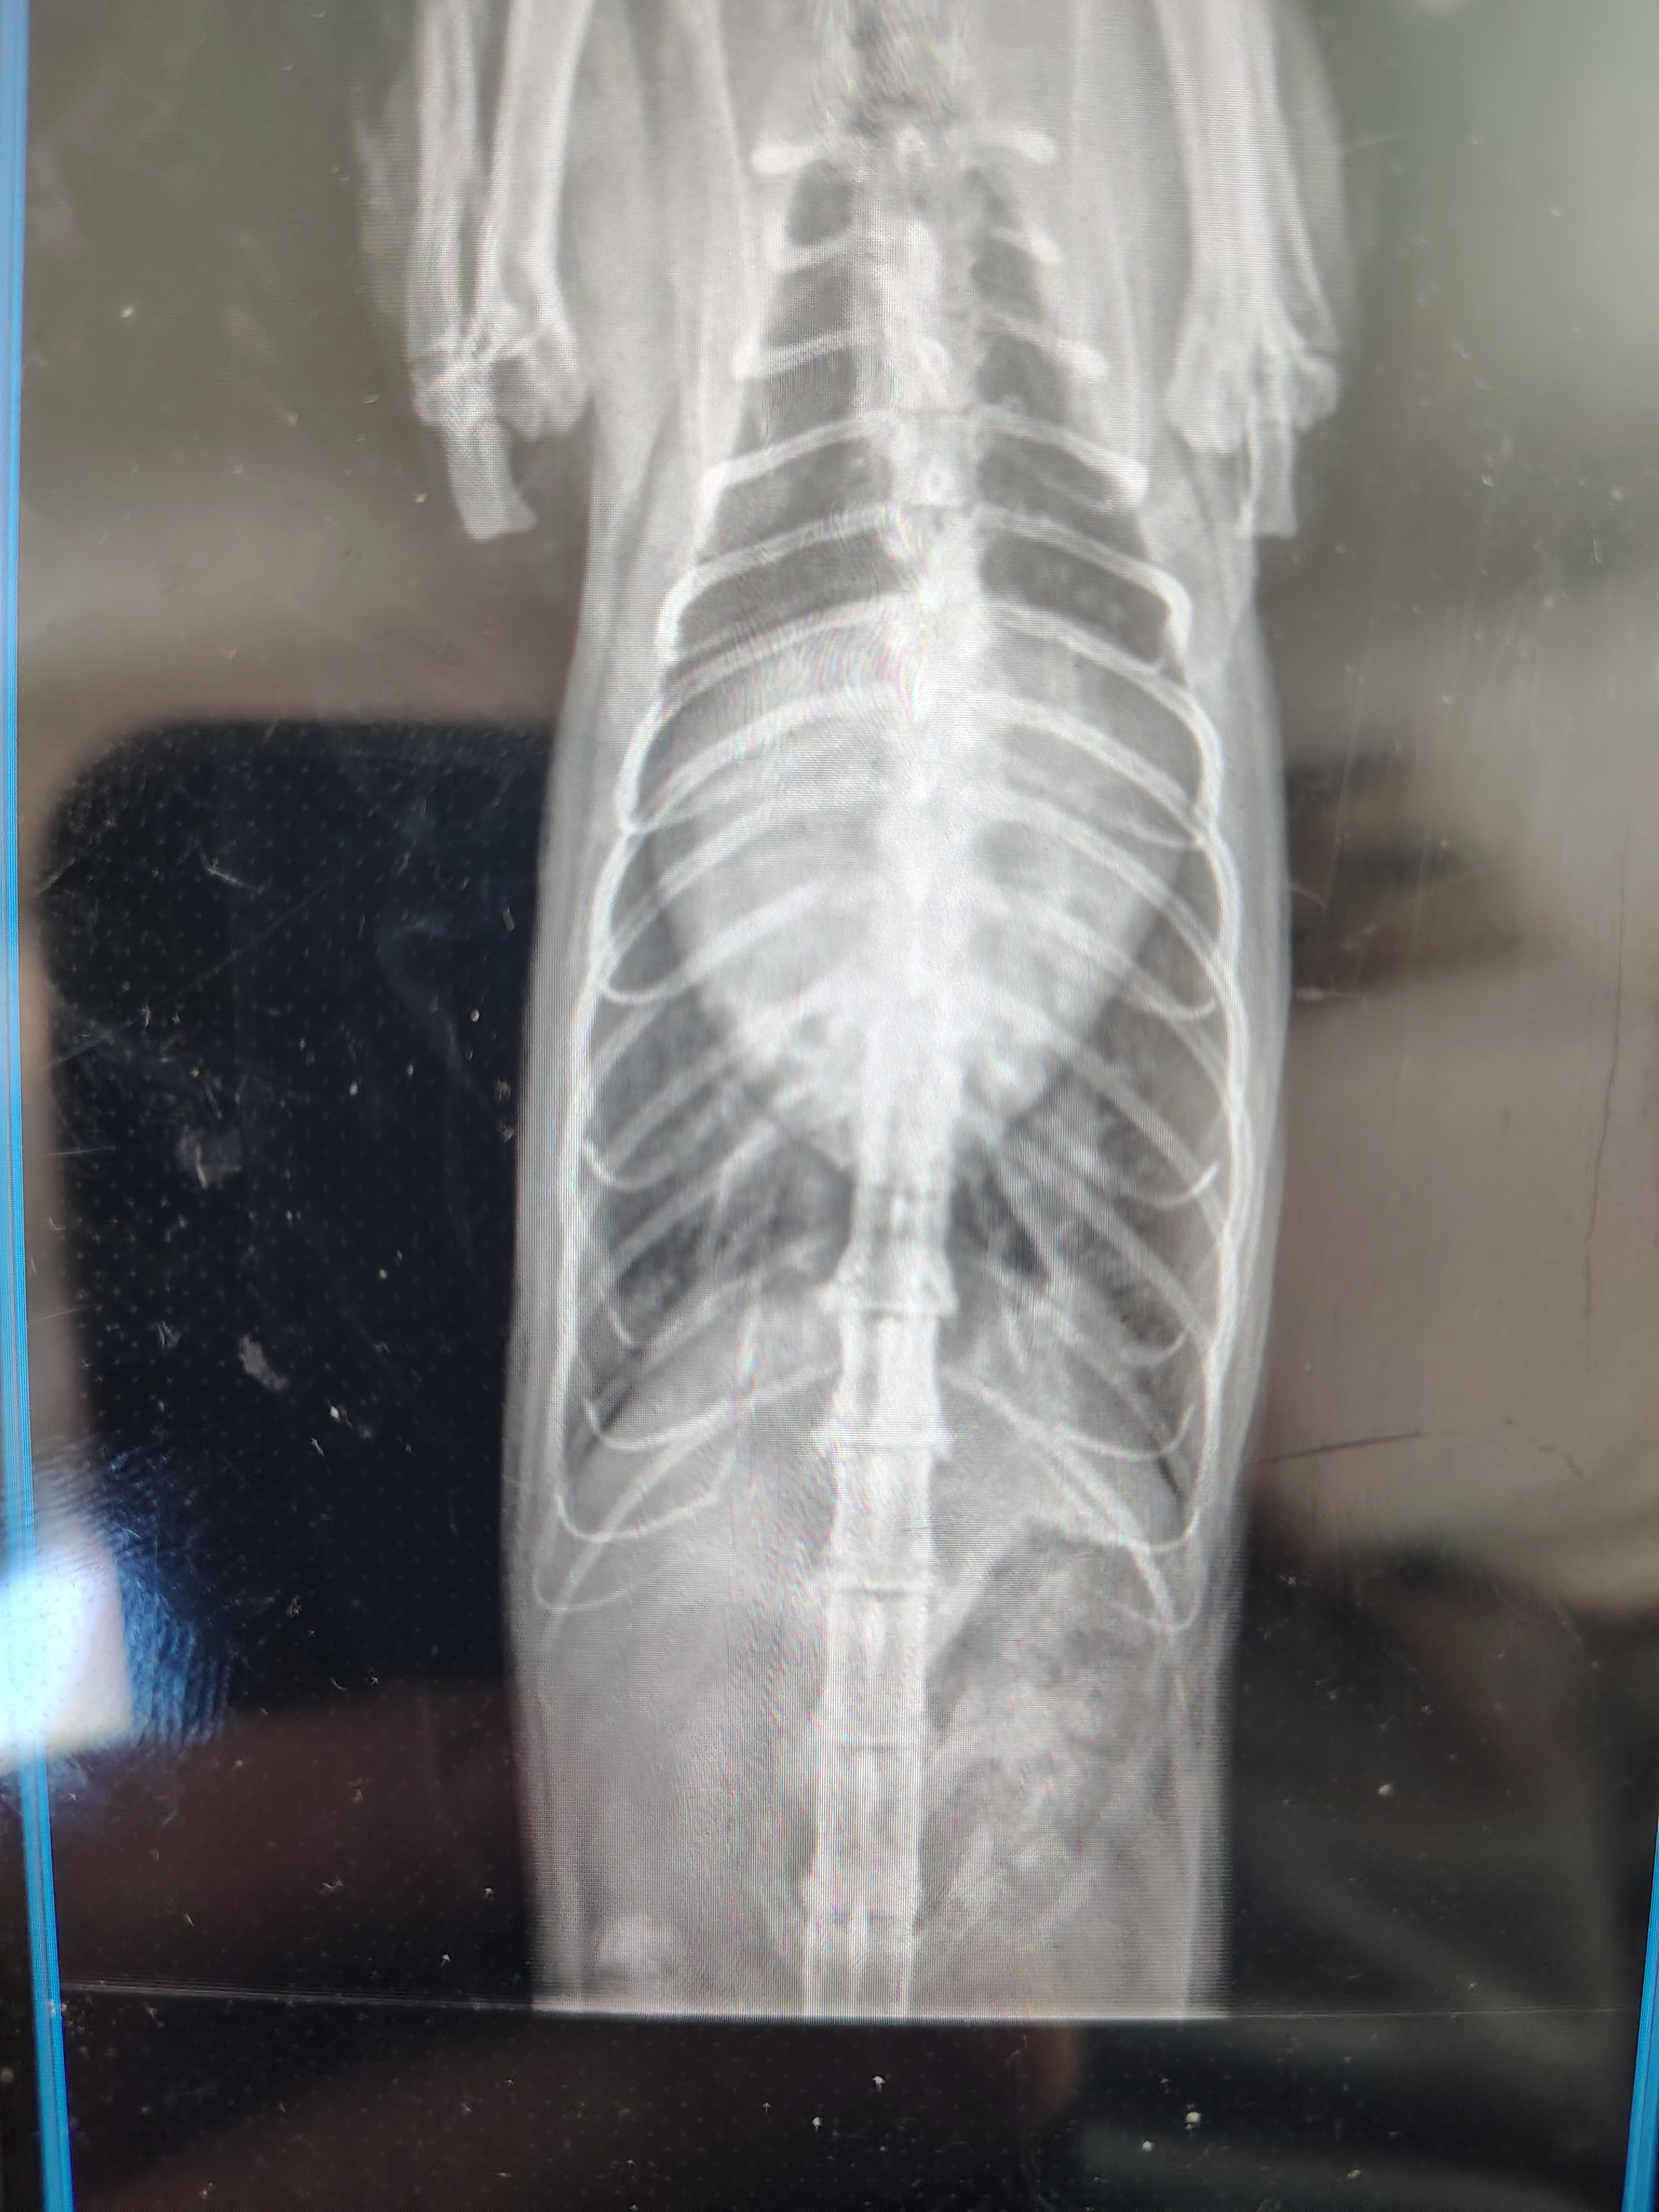

They performed X-rays and suspect that Hypertrophic Cardiomyopathy (HCM) may be the cause, but they can’t say for certain yet. Because Mijo’s breathing was so irregular, they weren’t able to safely complete a heart ultrasound. For now, he’s been started on medication for HCM and we were told to come back in a month. (f he’s strong enough to make it that long.)

Our vet also recommended additional testing to figure out what’s really going on, including blood work to rule out thyroid issues and a heart ultrasound once he’s stable. Without these tests, we’re left guessing and hoping the medication he’s on is the right one.

Like many people right now, the cost is overwhelming. So far the X-ray and exam have been $450, the blood test is $200, and the heart ultrasound will be $650. We just want answers so we can give Mijo the right treatment and the best chance to recover.